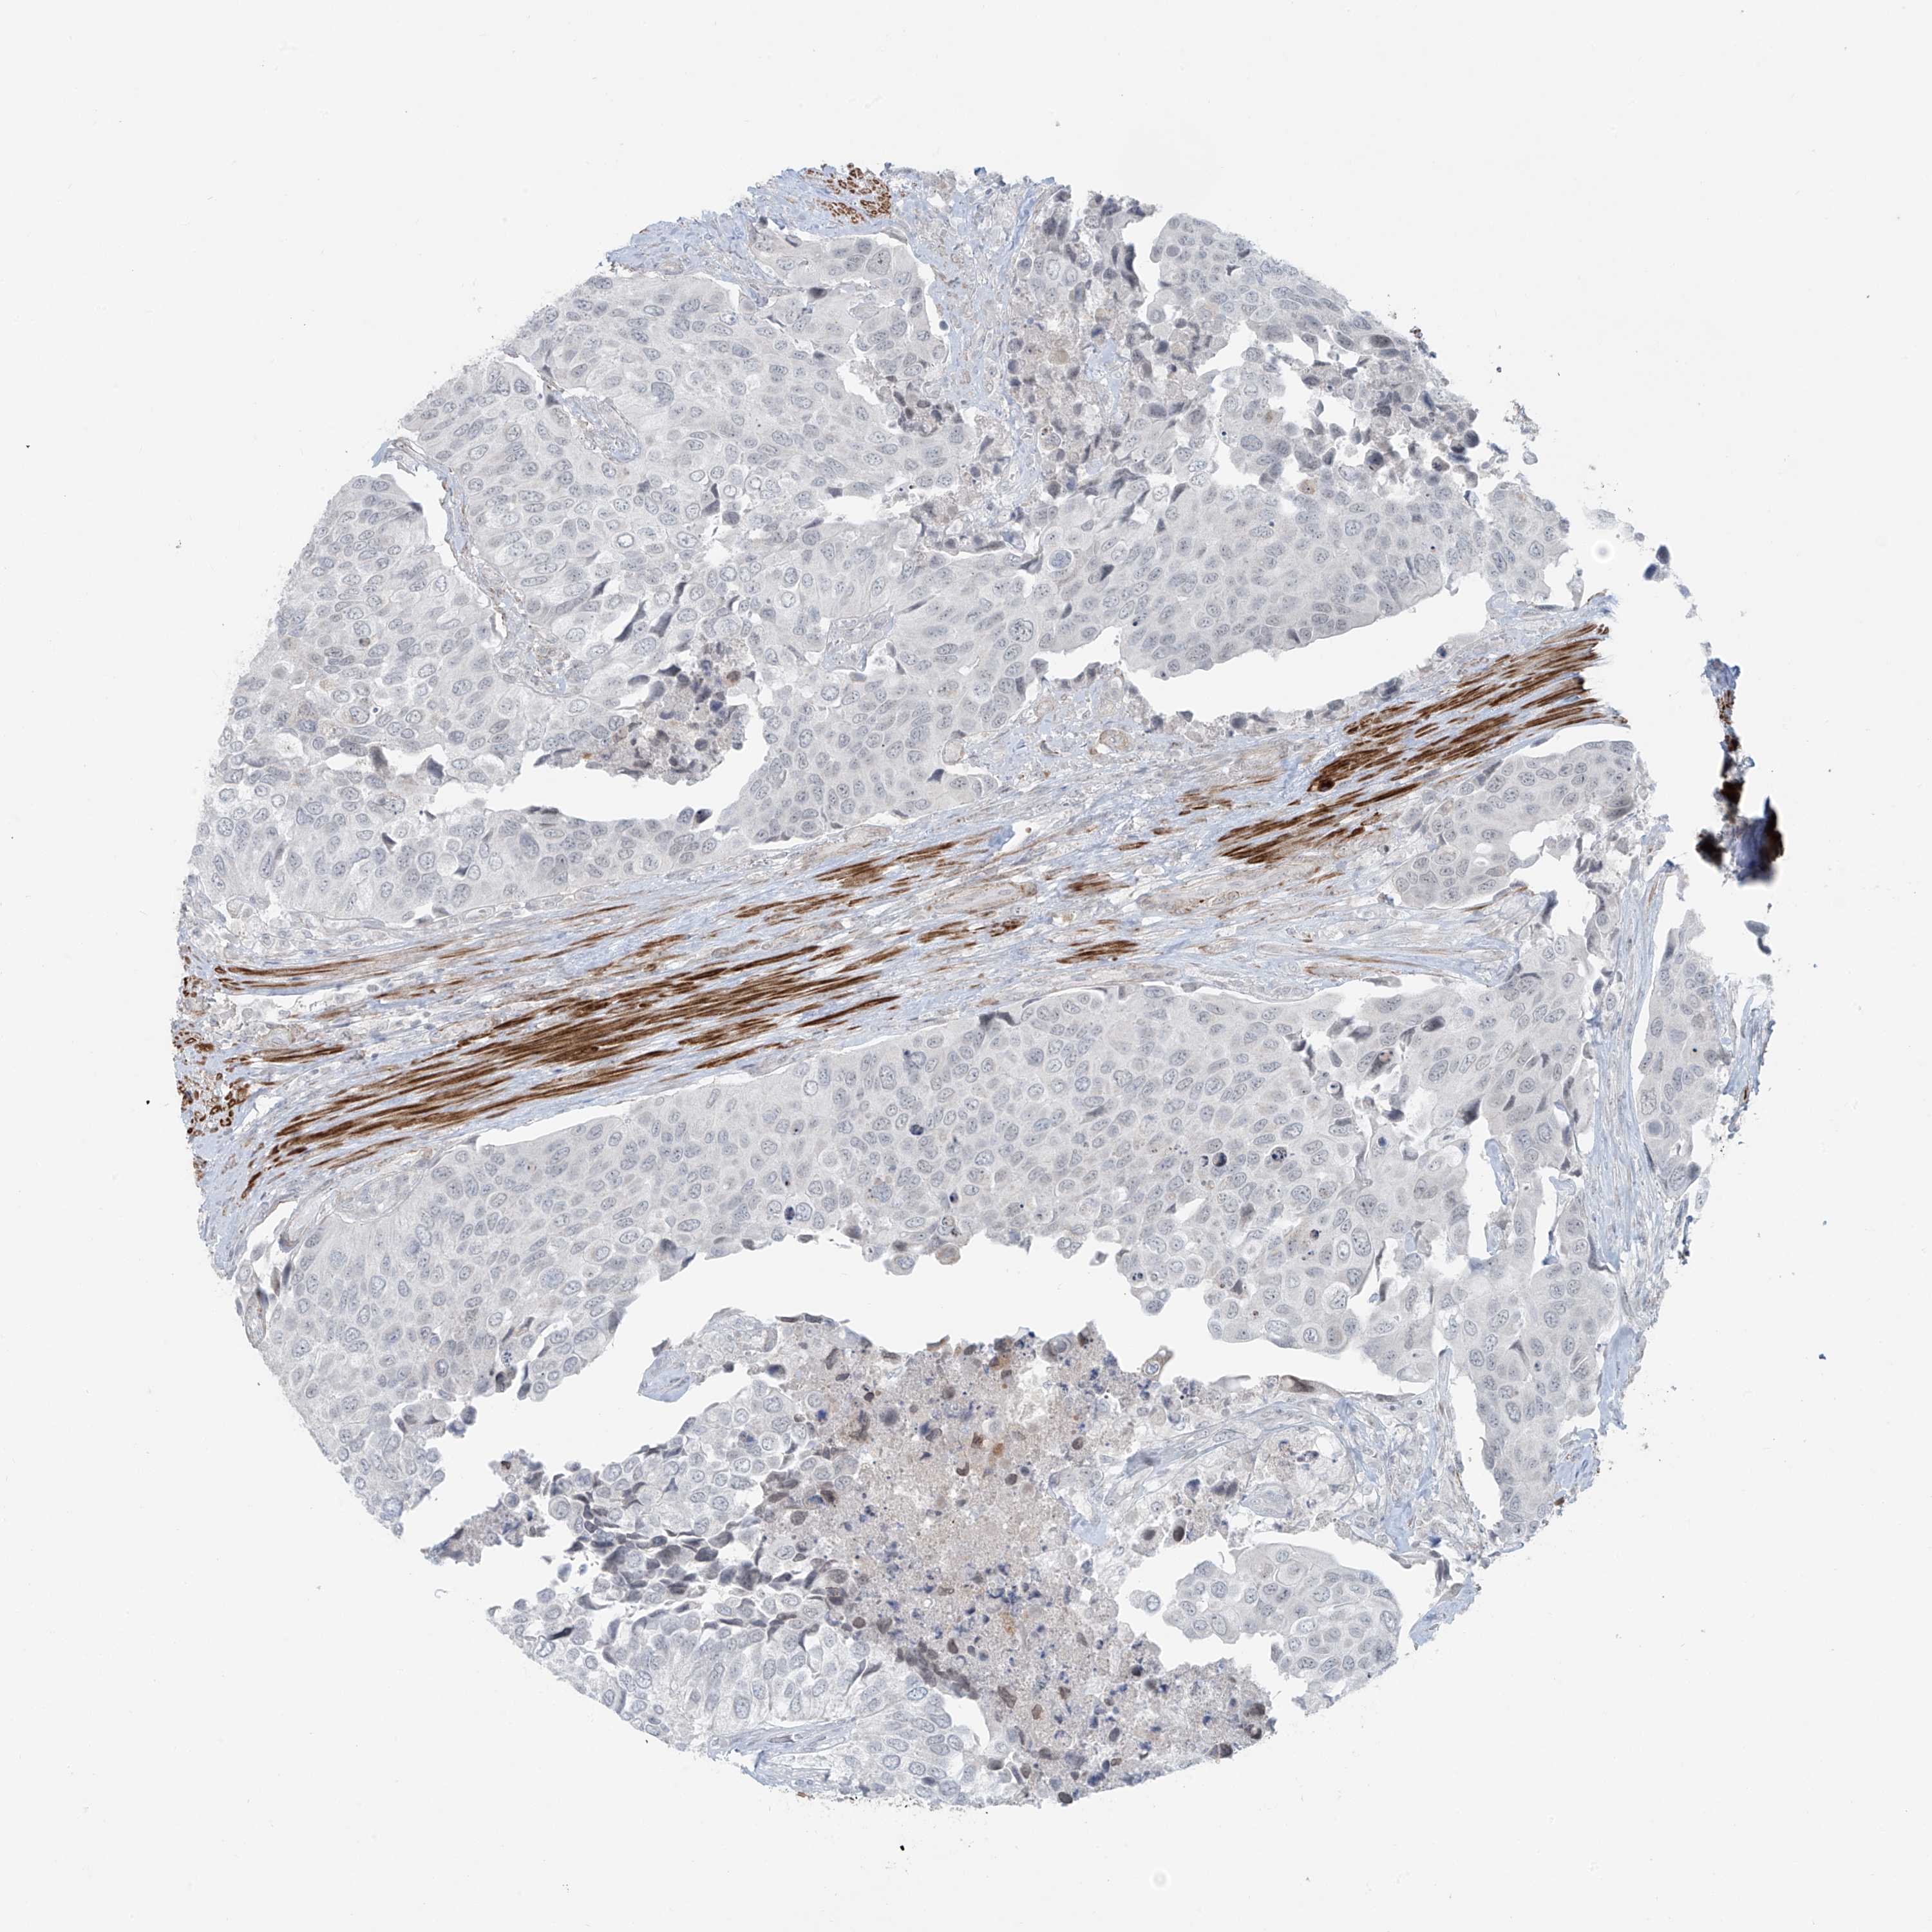

UROTHELIAL CANCER - Protein expressioni

A mouse-over function shows sample information and annotation data. Click on an image to view it in a full screen mode. Samples can be filtered based on level of antibody staining by selecting one or several of the following categories: high, medium, low and not detected. The assay and annotation is described here.

Note that samples used for immunohistochemistry by the Human Protein Atlas do not correspond to samples in the TCGA dataset.

Antibody stainingi

Antibody staining in the annotated cell types in the current human tissue is reported as not detected, low, medium, or high, based on conventional immunohistochemistry profiling in selected tissues. This score is based on the combination of the staining intensity and fraction of stained cells.

Each image is clickable and will lead to virtual microscopy that enables deeper exploration of all samples and also displays staining intensity scores, fraction scores and subcellular localization as well as patient and tissue information for each sample.

Antibody HPA035593

Staining

High

Medium

Low

Not detected

Intensity

Strong

Moderate

Weak

Negative

Quantity

>75%

75%-25%

<25%

None

Location

Nuclear

Cytoplasmic/membranous

Cytoplasmic/membranous,nuclear

Urothelial carcinoma, High grade

Urothelial carcinoma, Low grade